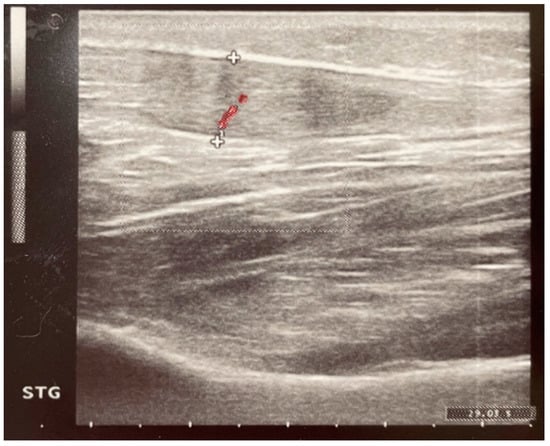

2.4. Paraclinical Evaluation—Ultrasound